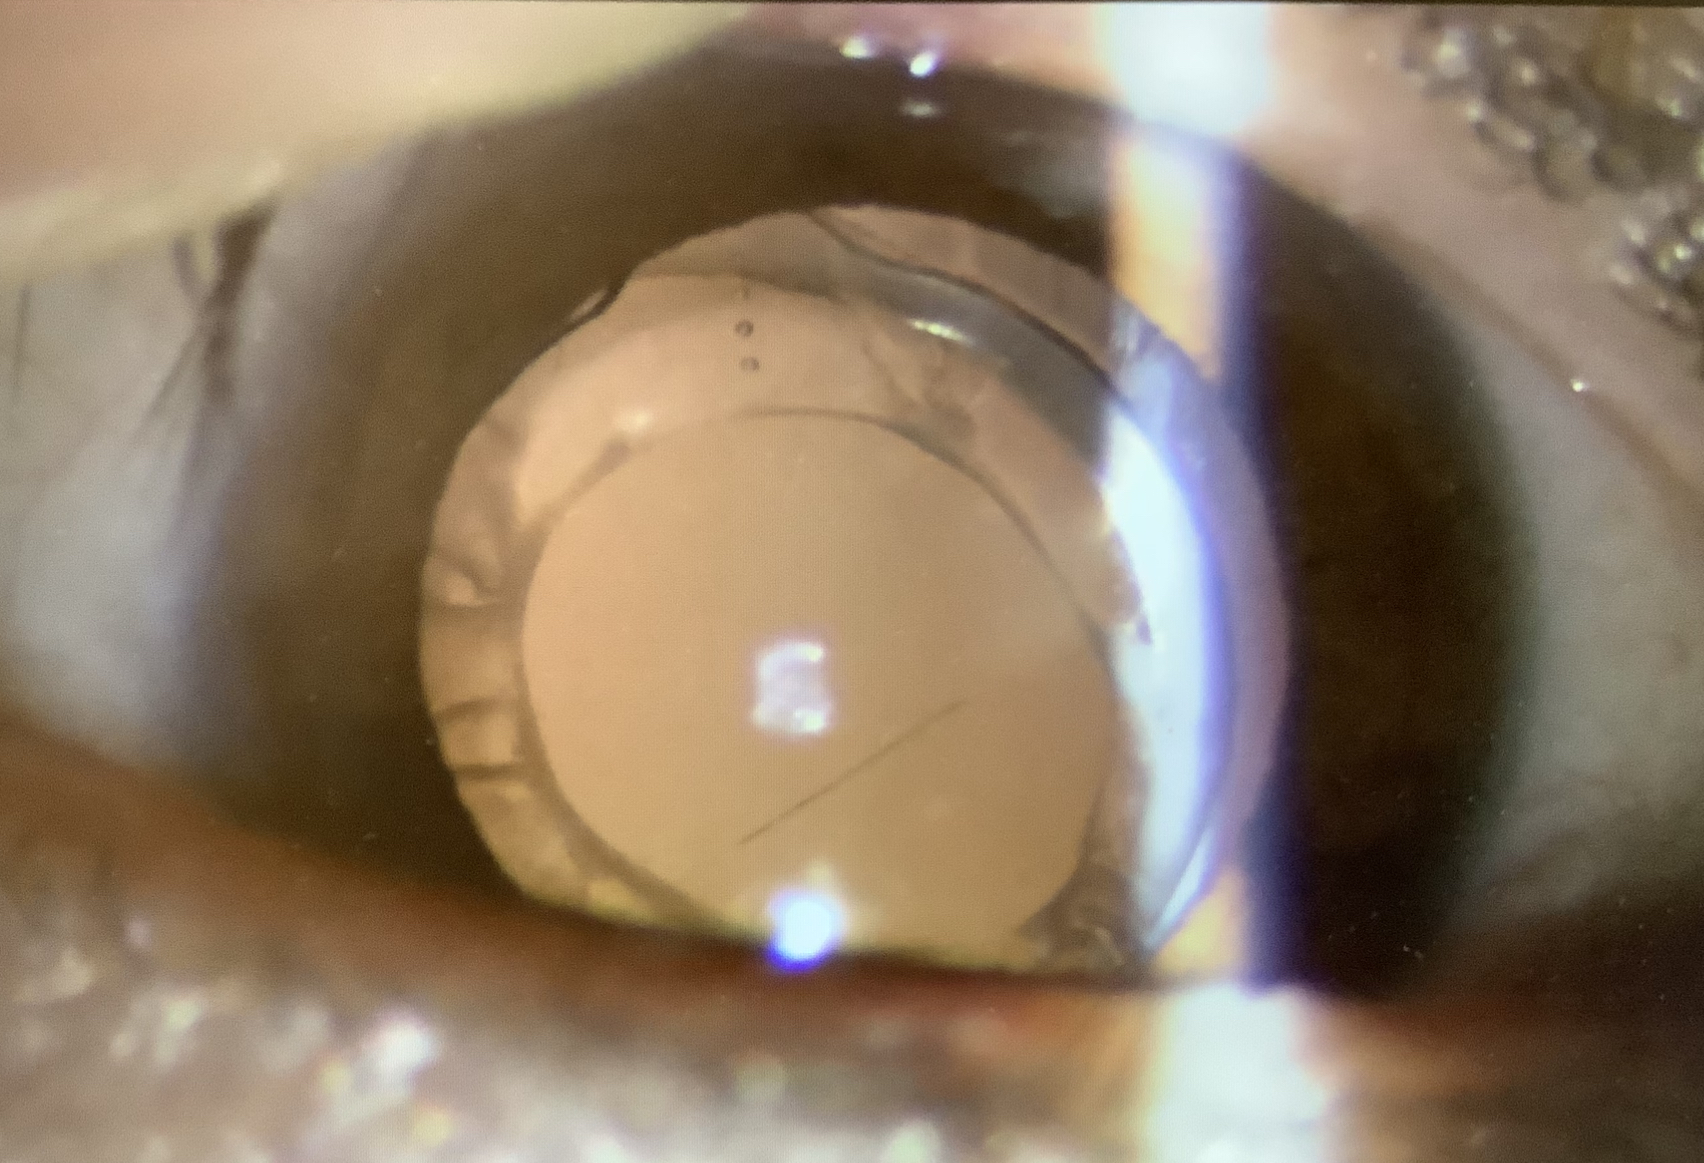

レンズがグラグラ揺れるレンズ振盪の所見があれば、チン小帯が弱いのは明らかで、そのような状況では入れ換えはかなり厳しいというか、無理と考えた方がよいですが(単純な単焦点レンズで強膜内固定前提であれば可ですが)、レンズ交換をするにあたって、その難易度の指標にしているのが、前嚢収縮です。白内障の手術の時に水晶体の表面の水晶体嚢を丸く切り抜きますが(連続円形前嚢切開:CCC)、一般的な眼内レンズの直径が6mmなので、僕はこのCCCの大きさは直径5.5mmを目指しています。そうすると、レンズの縁がわずかに前嚢で覆われるような状態になりますが、水晶体嚢にはわずかに水晶体上皮細胞が残り、時間の経過で多かれ少なかれ、水晶体嚢の濁りを生じます。前嚢にこの濁りが生じると、前嚢を収縮させ(前嚢収縮)、CCCの大きさが小さくなる方向に進みます(後嚢側の増殖が強くなれば、後発白内障になります)。とはいっても、通常は前嚢に濁りが生じてもそれほどCCCの大きさは変わらないのですが、チン小帯が弱いと、おそらく、外側に引っ張る力が弱くなるため、前嚢収縮が強くなり、CCCが小さくなる傾向があるかと思います。なので、前嚢の混濁や収縮が強いということはチン小帯が弱い可能性が高く、レンズの入れ換えがしにくく、手術が大変になる可能性を示していると考えています。もちろん、絶対に入れ換えできないということではなく、どうしてもの場合は、手術もしますが、うまくいかない可能性、具体的に言うと、チン小帯が外れて、レンズを眼の壁に固定する強膜内固定をしないといけなくなる可能性はそれなりに覚悟が必要かと思います(その確率が何%ということはなかなか言えないですし、具体的な数字があったとしても、それはあまり意味のないことだと思います)。